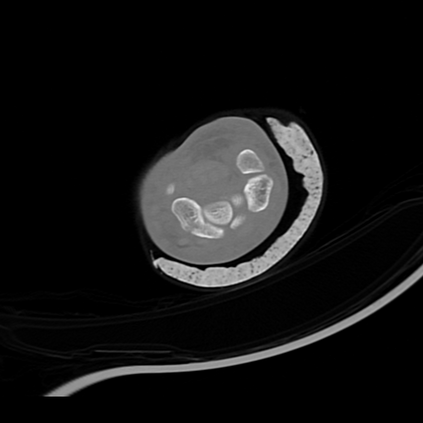

CT reconstruction provides radiologists with images for diagnosis and treatment, yet current deep learning methods are typically limited to specific anatomies and datasets, hindering generalization ability to unseen anatomies and lesions. To address this, we introduce the Multi-Organ medical image REconstruction (MORE) dataset, comprising CT scans across 9 diverse anatomies with 15 lesion types. This dataset serves two key purposes: (1) enabling robust training of deep learning models on extensive, heterogeneous data, and (2) facilitating rigorous evaluation of model generalization for CT reconstruction. We further establish a strong baseline solution that outperforms prior approaches under these challenging conditions. Our results demonstrate that: (1) a comprehensive dataset helps improve the generalization capability of models, and (2) optimization-based methods offer enhanced robustness for unseen anatomies. The MORE dataset is freely accessible under CC-BY-NC 4.0 at our project page https://more-med.github.io/